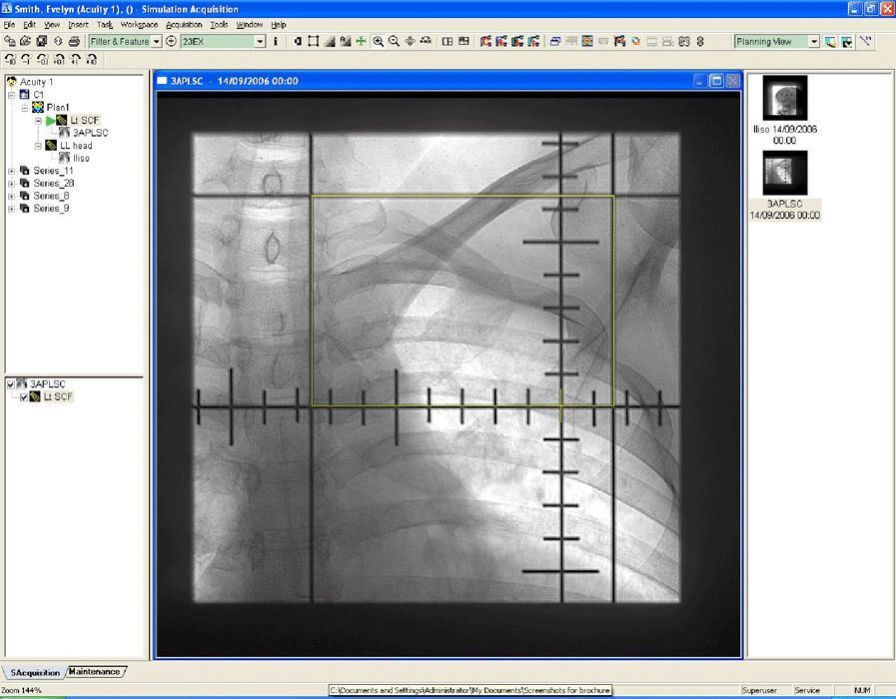

From axisimagingnews.com

Varian Launches Cancer Imaging Software Axis Imaging News Varian Medical Systems India Software Var ), a world leader in radiotherapy equipment and software, has. From software and machines to patient data and care teams, intelligent cancer care is uniting the world's cancer fight. Fortis international oncology centre, a joint initiative between international oncology and fortis healthcare, is equipped with advanced. We offer a wide range of software solutions to help meet your clinical. Varian Medical Systems India Software.